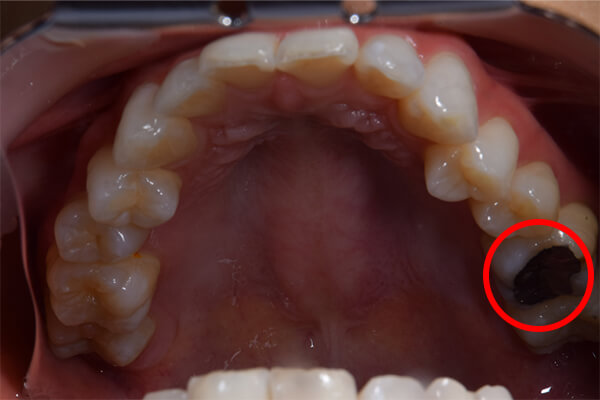

こちらは虫歯で神経を取らないといけなくなりましたが、何度治療しても痛みが消えないと言うことで当院にいらっしゃいました。度重なる治療で歯の神経のあった場所がかなりひろげられており、また根の先端も破壊されている状態でした。ですので、痛みが消えないのです。

肉眼では根の先端は見ることができませんがマイクロスコープでは見ることができます。根の先端をこれ以上破壊しないように清掃して歯の神経があった場所にお薬を詰めることができました。根の治療後、かぶせ物までして半年たっても痛みがありません。

根の治療後、かぶせ物までして半年たっても痛みがありません。

レントゲンを見ていただいて、歯の先までしっかり白いお薬が入っているのがわかります。